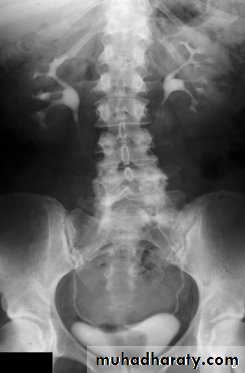

Bulb of follys cathter IVU with bilateral mild to moderate degree of HN

RT sided PUJ stenosis & obstruction with RT sided HN

Uretrocele (cobra head shape)distal both sided ureteric ends with dilated both ureters

Uretrocele